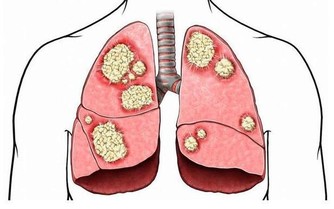

4、肝膽疾病

中醫認為,口乾、口苦是肝膽火旺的典型症狀。當人體的肝臟功能出現問題時,體內的代謝物、毒素、垃圾就不能及時排出並且堆積,從而引起口苦。

另外,很多時候,膽囊疾病病人都有口苦的現象。尤其是老年人,由於胃動力差或者膽汁反流所引起口苦。